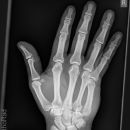

subcapitale MC 5 Fraktur